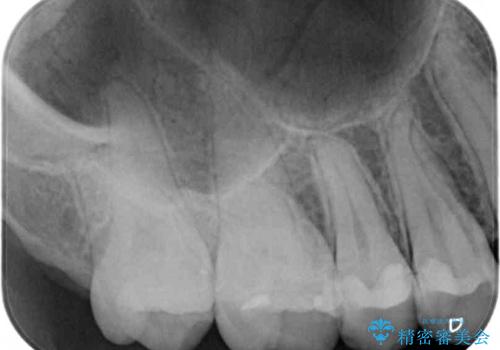

- 奥歯にフロスが引っかかるようになり、虫歯ではないかとのことで来院された患者様です。

レントゲン写真より、左右奥歯にむし歯があることが分かりました。

奥で目立たないことから、虫歯の再発リスクが最も低く、咬合力による歯への負担も少ないゴールドインレー(PGAインレー、白金加金インレー)にて修復治療をすることとしました。